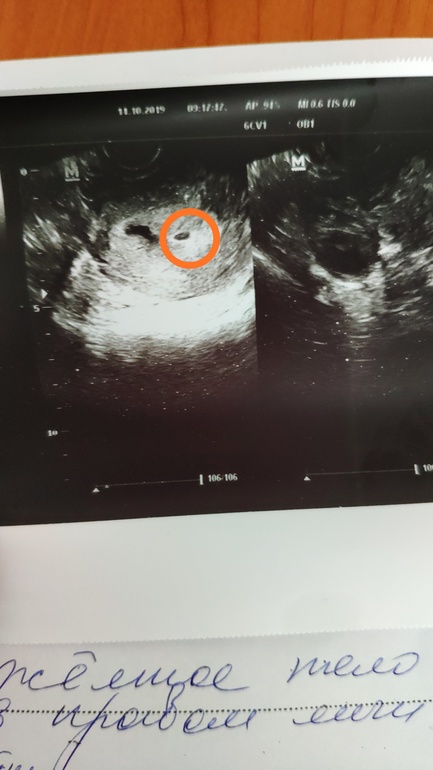

Сегодня мне у двух врачей подтвердили ЗБ....С одной стороны понимаю,что значит так надо было,а с другой.....слов нет....сижу плачу... Моя первая и, надеюсь,единственная,замершая ....

Будем продолжать значит дальше пробовать,стараться